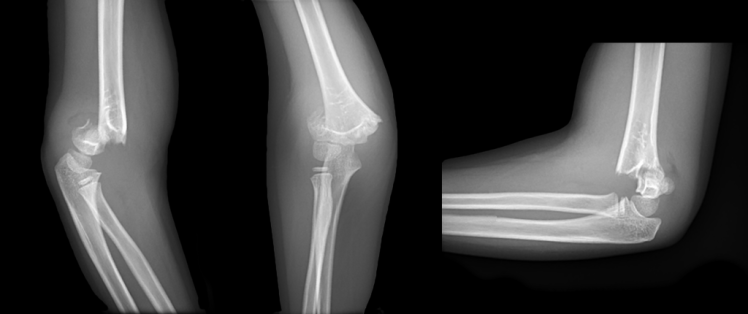

Val op uitgestrekte arm, wat is de diagnose? Gepost op 18 juni 201718 juni 2017 door netwerkvsseh Wat is de diagnose? @ emdaily.cooperhealth.org Dit delen: Delen op X (Opent in een nieuw venster) X Share op Facebook (Opent in een nieuw venster) Facebook Delen op LinkedIn (Opent in een nieuw venster) LinkedIn E-mail een link naar een vriend (Opent in een nieuw venster) E-mail Afdrukken (Opent in een nieuw venster) Print Vind-ik-leuk Aan het laden... Gerelateerd